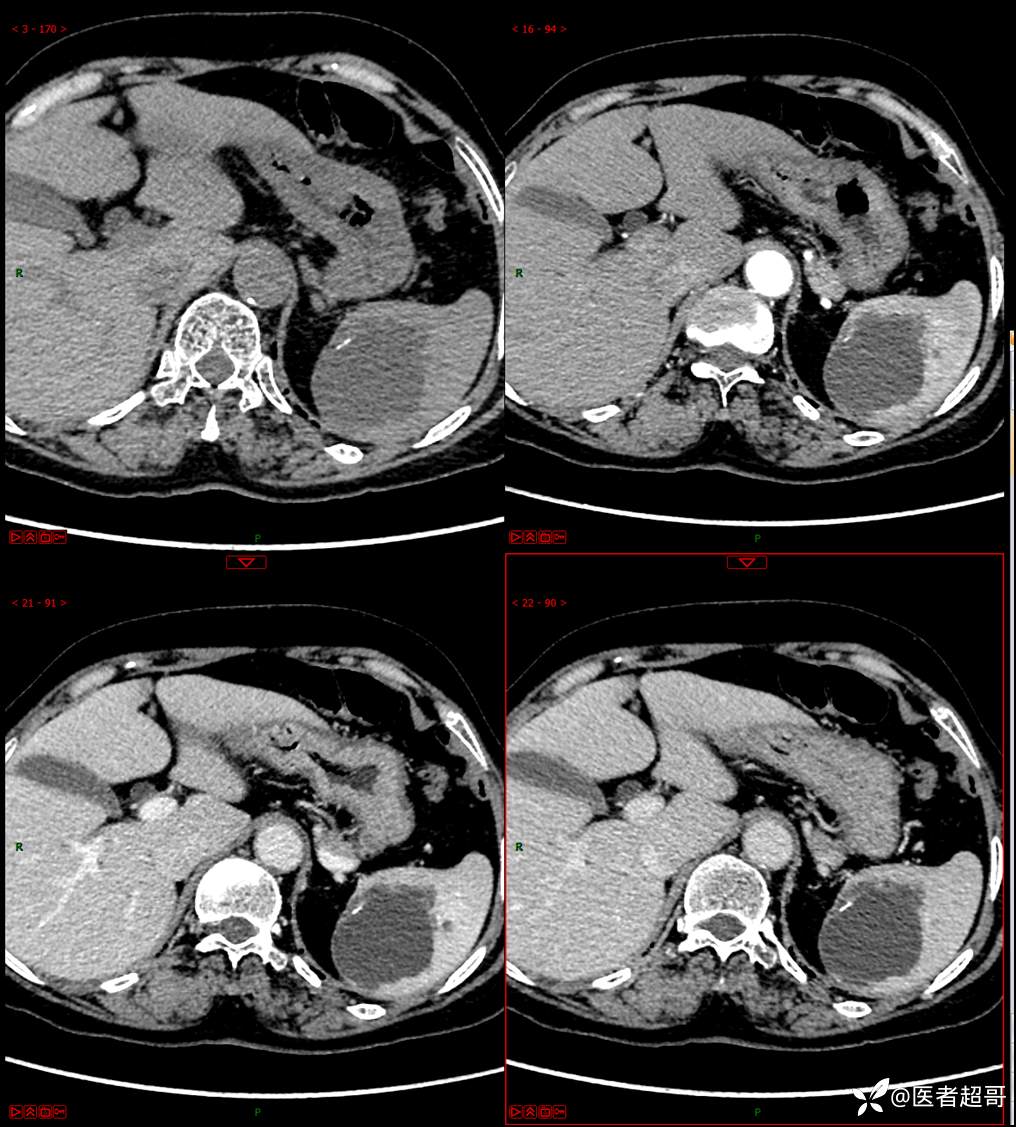

现病史:患者9天前于市人民医院查体时发现脾脏肿物,未行处理,后于我院门诊查,上腹部CT平扫+强化:脾脏占位,考虑良性,囊肿?脉管源性病变?患者诉平素无异常不适。现患者为求进一步诊疗,门诊遂以“脾肿物”收入院。患者自患病以来,神志清,精神可,饮食、睡眠可,大小便正常,体重未见明显变化。